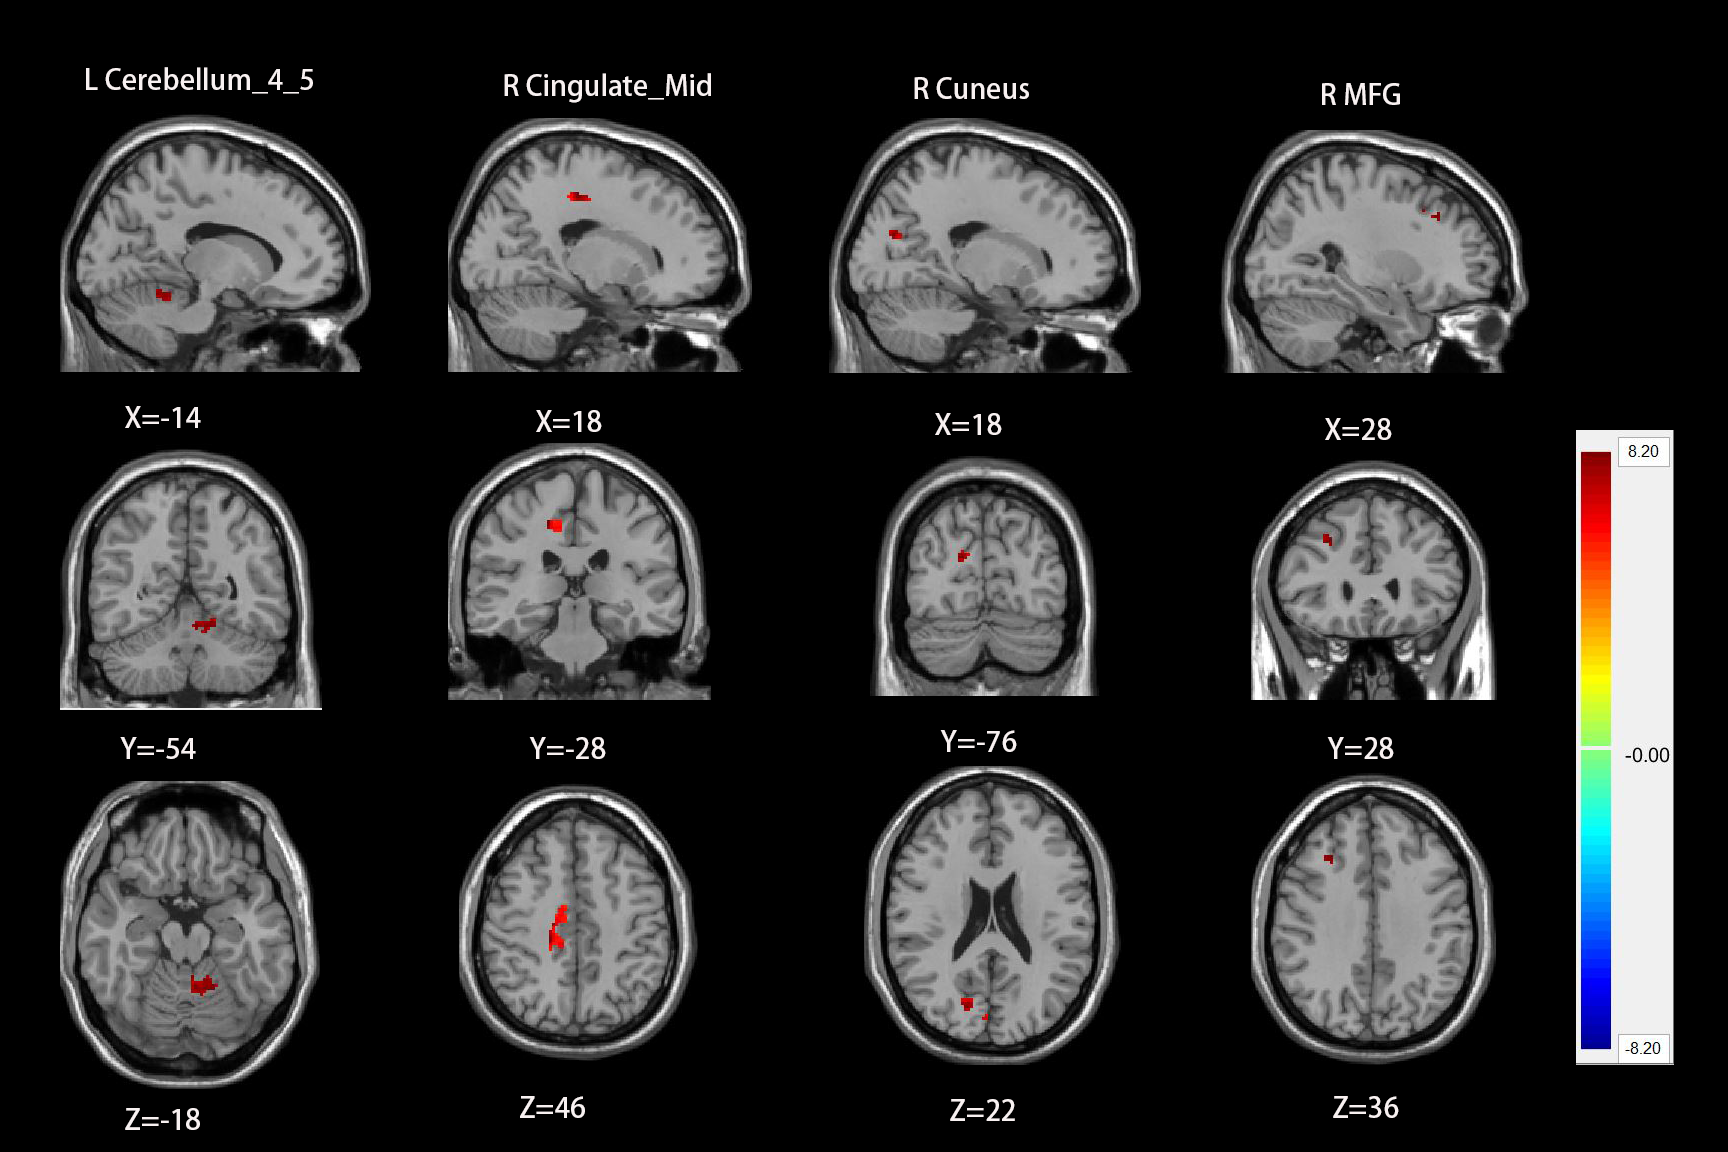

RESULTS: Compared with healthy controls, chronic tinnitus patients with hearing loss showed a significantly increased ALFF values in the right hippocampus, left middle temporal gyrus (MTG), left middle frontal gyrus (MFG), and bilateral precuneus, and a significantly increased ReHo values in left PAC, bilateral MTG, left superior temporal gyrus (STG), right amygdala and left angular gyrus (AG). Based on FC analysis, the left PAC showed reduced functional connectivity with non-auditory brain regions including the right MFG, right cingulate cortex, right cuneus and left cerebellum in the groups of chronic tinnitus with hearing loss compared with healthy controls.

Figure3 the left PAC showed reduced FC with right MFG, right cingulate cortex, right cuneus and left cerebellum